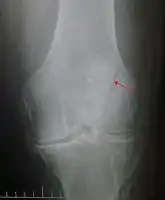

| A fracture of the patella seen on a lateral view | |